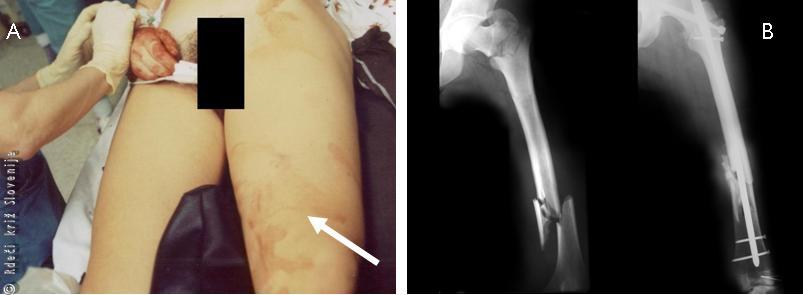

Slika 4

A – Izgled zadebeljenega stega po zlomu stegnenice.

B – RTG posnetek stegnenice pred in po operaciji.